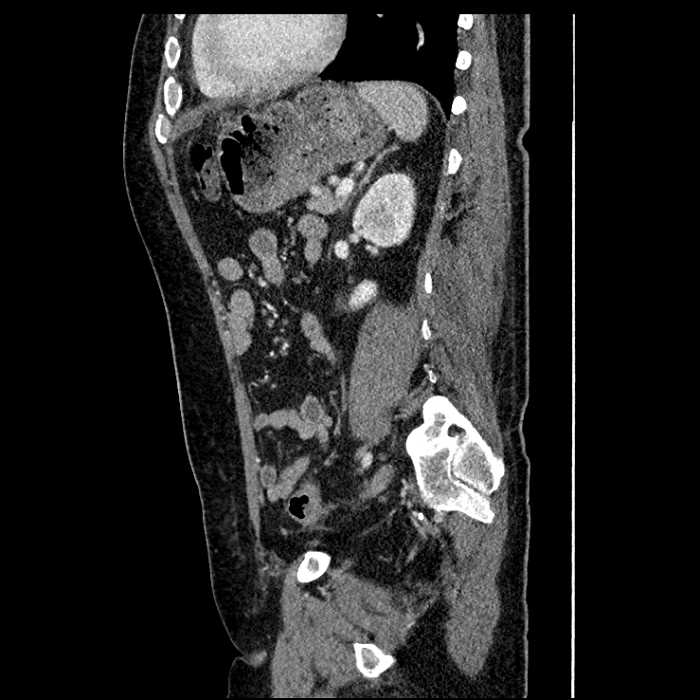

Age: 63

Sex: Male

Indication: Abdominal pain

• Large fluid density structure in hepatic segments 7 and 8 measuring 10 x 7 x 7 cm with internal septation and circumferential ill-defined low density compatible with edema

• Peripherally enhancing subcapsular collections along the anterior margin of the left hepatic lobe measuring 3 x 1 cm and 2 x 1 cm

• Mild mural thickening of a segment of the sigmoid colon with adjacent fat stranding and a 1.5 cm fluid and gas collection along the tip of an inflamed diverticulum

• Loss of the normal fat plane between this collection and adjacent loops of small bowel, which demonstrate mural thickening

Acute sigmoid diverticulitis complicated by a small contained perforation and a large abscess in the right hepatic lobe. Additional small subcapsular abscesses along the anterior margin of the left hepatic lobe.

Additionally, loss of the normal fat plane between the peridiverticular collection and adjacent thickened loops of small bowel raises the potential for an enterocolonic fistula.

• The classic CT imaging appearance is a double target sign with internal low density surrounded by an internal enhancing rim (capsule) and a low density external rim (edema)

Hepatic abscess showing the double target sign with low density internally surrounded by a thin inner enhancing rim (red arrow) and ill-defined outer low density rim (yellow arrow). Blue arrow indicates an internal septation. Red arrows: additional smaller subcapsular abscesses. Red arrow: focal contained perforation associated with diverticulitis.